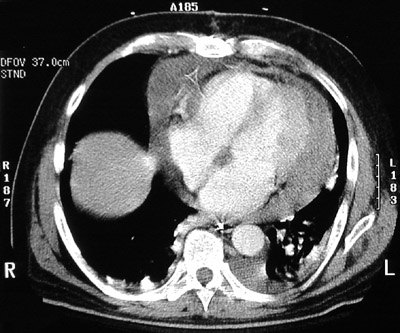

This chest CT scan demonstrates a large pericardial effusion around the heart. The dome of the liver appears at the right.